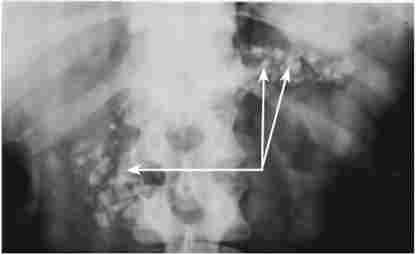

Істотне діагностичне значення має рентгенологічне дослідження шлунка і особливо дванадцятипалої кишки. При рентгенографії шлунка виключаються його органічні ураження, що можуть мати відношення до патогенезу панкреатиту, і іноді виявляються деформації, пов'язані зі змінами в підшлунковій залозі (рис. 20.4), наприклад вдавлення при наявності псевдокист, опухолевидной форми ХП і т. Д.

Деформація контуру вихідного відділу шлунка і розворот дванадцятипалої кишки при кісті головки підшлункової залози

Мал. 20.4. Деформація контуру вихідного відділу шлунка і розворот дванадцятипалої кишки при кісті головки підшлункової залози

Дуоденографія дає можливість судити про вільному пасажі барію через дванадцятипалу кишку або про наявність дуоденостаза, як уже згадувалося, має значення в патогенезі ХП. Інформативним методом виступає рентгенологічне дослідження дванадцятипалої кишки в умовах медикаментозної (штучної) гіпотонії, що досягається попереднім введенням спазмолітиків, наприклад атропіну. До характерними ознаками хронічного панкреатиту, виявлення яких сприяє гіпотонія, відносяться розширення підкови дванадцятипалої кишки внаслідок збільшення розмірів головки ПЖ і наявність на медіальній стінці спадного відділу кишки широкого дефекту наповнення, іноді стенозирующего просвіт і утрудняє пасаж барію (рис. 20.5).

Дуодеіографія з гіпотонією

Мал. 20.5. Дуодеіографія з гіпотонією. На знімку видно розширення підкови дванадцятипалої кишки і здавлення кишки на рівні низхідній і нижньої горизонтальної її гілок збільшеною головкою підшлункової залози